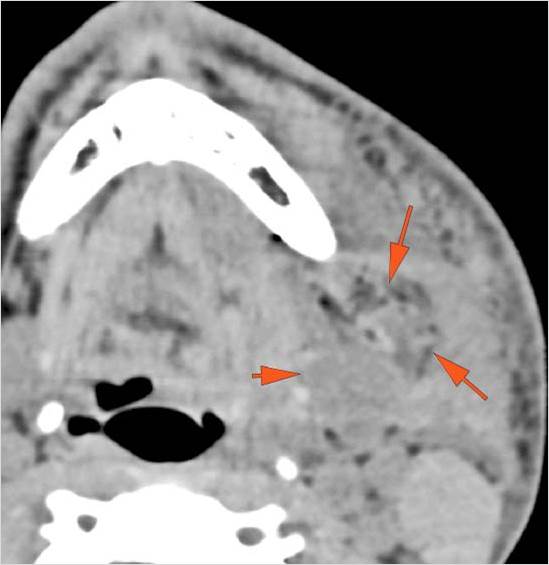

34-year-old male in the ER following an altercation with possible mandibular or other facial fractures due to craniofacial trauma.Exam

34-year-old male in the ER following an altercation with possible mandibular or other facial fractures due to craniofacial trauma.